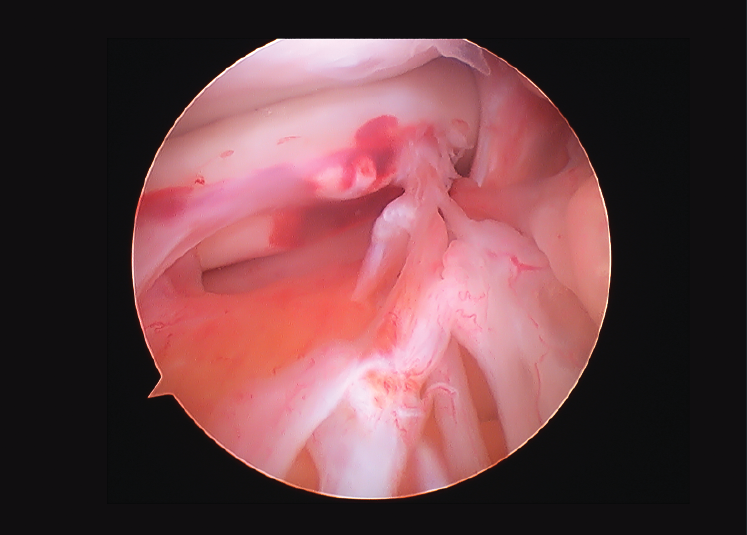

Neovasos hacia el fragmento luxado de una lesión en asa de cubo meniscal

Neovessels reaching the dislocated fragment of a meniscal bucket handle injury

Visión desde el portal anteromedial de una lesión crónica en asa de cubo meniscal de una rodilla izquierda, en la que se observa cómo se han creado neovasos desde la grasa de Hoffa hasta el fragmento luxado de la lesión.